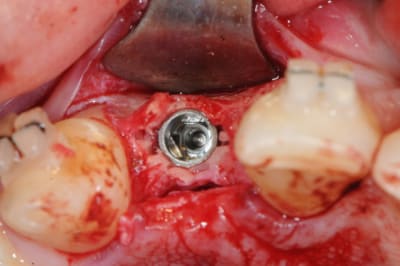

ou comme ça encore...

( agénésie de 12 - expansion osseuse sur une crête fine ) agénésie...

la suite à Sallanches les 2 et 3 Février pour ceux qui veulent encore s’inscrire)

très beau!

joli bombé vestibulaire, il va falloir que je fasse fort pour rester devant!